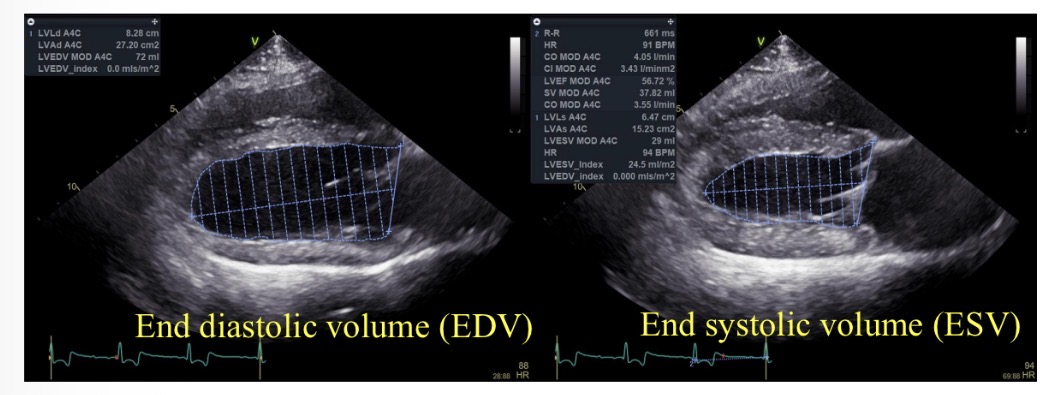

Ejection fraction (%) equation

((EDV-ESV) / EDV) x 100

Normal ejection fraction

>50%